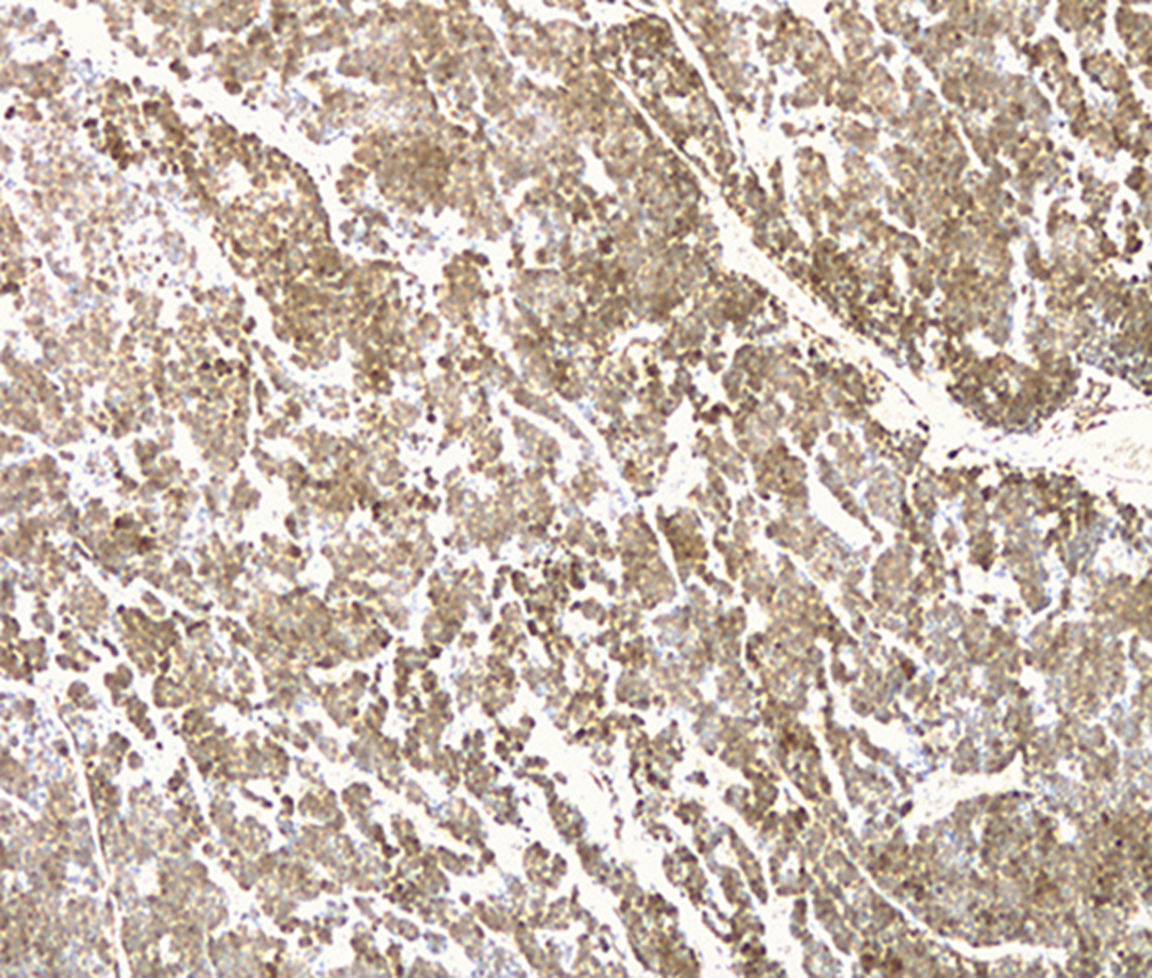

A 37-year-old leucodermic woman with no relevant past history presented with 1-month history of new-onset epigastric pain and bloating. She denied any other symptoms. She underwent an esophagogastroduodenoscopy that revealed a 25-mm subepithelial lesion in the gastric antrum (Fig. 1). Tunnel biopsies were done and were unrevealing. She underwent an endoscopic ultrasound (EUS) that showed a 25-mm hypoechogenic subepithelial lesion originating in the muscularis propria (Fig. 2). EUS-guided fine-needle aspiration (FNA) with a 25-G needle (Boston Scientific®) was performed (2× passes using suction technique), revealing cell nests without atypia, that were focally positive for smooth-muscle actin and synaptophysin, and negative for chromogranin and CD117. KIT and PDGFRA mutations were also negative. Unfortunately, the sample was inadequate for further study. A staging CT was performed excluding distant metastasis. Since investigations thus far were inadequate to exclude a malignant process, she underwent laparoscopic-wedge gastrectomy. Histopathology revealed a solid, epithelioid, and richly vascular tumor without cellular atypia (Fig. 3). Immunohistochemistry was similar to that previously performed and complemented with positive calponin (Fig. 4) and negative cytokeratin AE1/AE3 (Fig. 5), making the diagnosis of a glomus tumor.

Glomus tumors are rare mesenchymal neoplasms that originate in modified smooth-muscle cells (1-3). Despite being highly vascularized, they are most often benign (3). They are frequently found in the skin and subcutaneous tissue, although they can also be located in the gastrointestinal tract, most commonly in the stomach (2, 3). Gastric glomus tumors are usually located in the antrum (2, 3). Clinical symptoms are nonspecific, ranging from dyspepsia to gastrointestinal bleeding (3). Endoscopically, they appear as a smooth submucosal lesion, usually 2-3 cm in size, and present as an ulcerated submucosal lesion in roughly 45% of cases (3). On EUS, they typically originate from the muscularis propria (4th echo layer) but can also be found in the submucosal or mucosal layers (1). Additionally, they can present either as hyperechoic or hypoechoic, usually have internal hyperechoic foci, and present a prominent Doppler signal consistent with the vascular nature of these tumors (1, 2). However, it can be difficult to distinguish them from other subepithelial lesions (e.g., gastrointestinal stromal and neuroendocrine tumors) since they do not exhibit specific distinguishing features on EUS (2). EUS-FNA is an effective method to obtain cytological specimens of gastric submucosal neoplasms, allowing for an adequate histopathological evaluation when using the cell-block technique. However, to ensure an adequate diagnosis of a gastric submucosal lesion, it is important to perform an immunohistochemical study on the cell block (4). Gastric glomus tumors are typically positive for actin, calponin, and vimentin, and negative for CD117, CD20, and CD45, chromogranin A, desmin, and S-100 protein, allowing the distinction of these tumors in the differential diagnosis (3). Since malignant transformation has been described, a complete resection of the lesion is mandatory for definitive treatment (2, 3). The surgical approach depends on the location and size of the tumor. Zhang et al. (2) reported an effective endoscopic approach through endoscopic submucosal dissection technique. However, due to its infrequency, there are insufficient data to establish guidelines regarding management, including the need for postoperative surveillance.